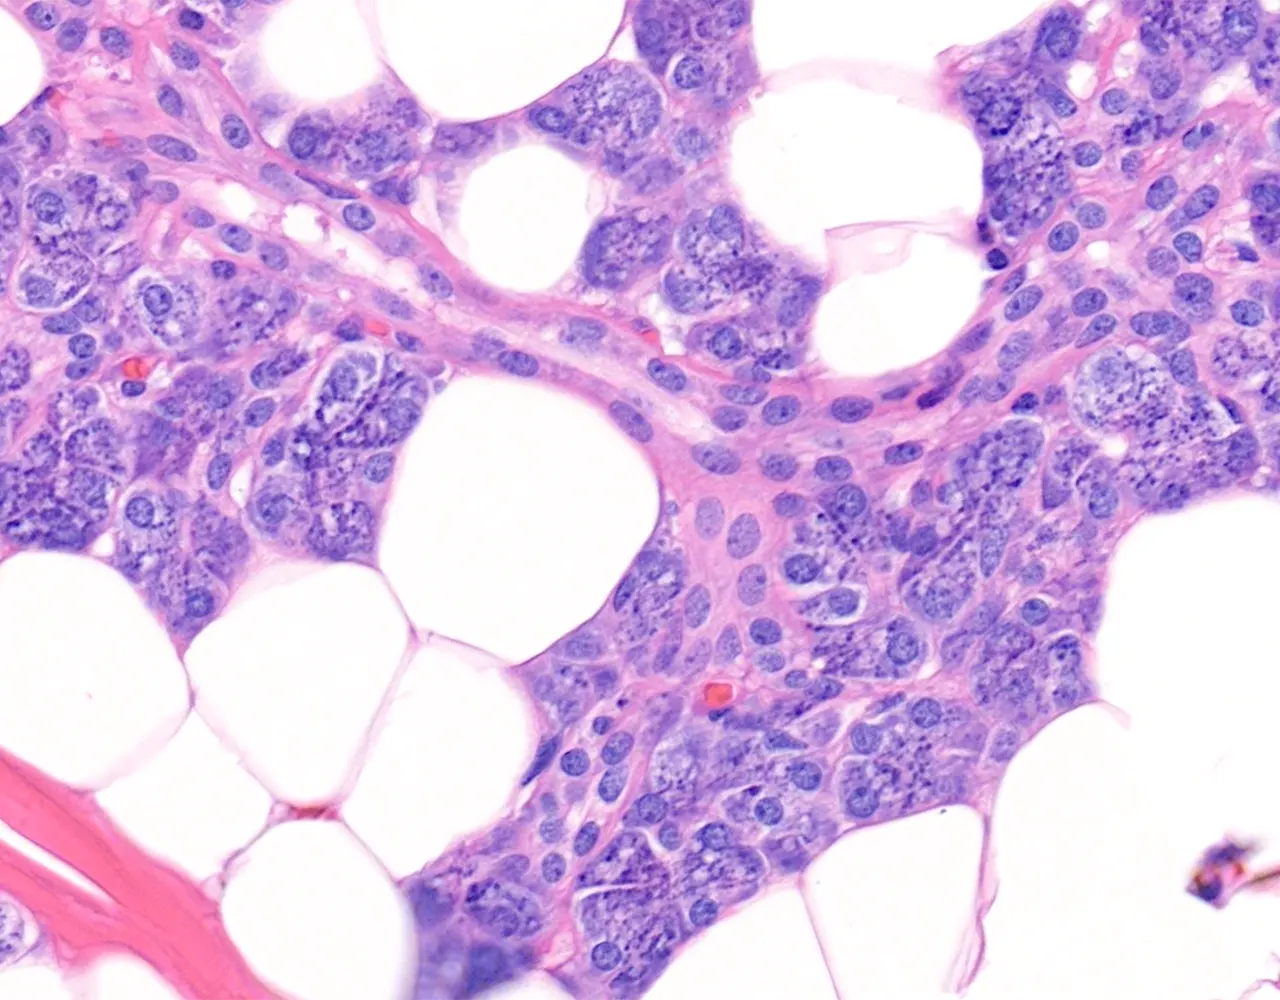

- Microscopically, the functional structure of a salivary gland consists of secretory acini and a duct system.